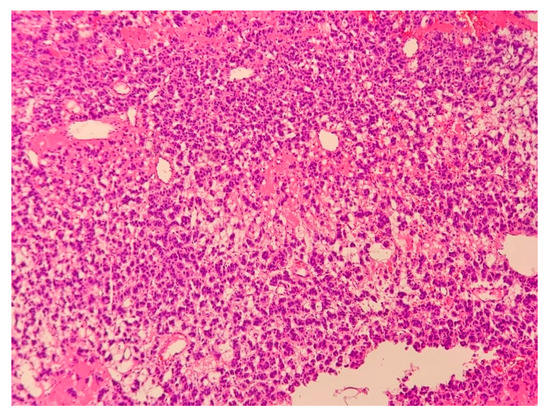

2.1. Case 1

2.2. Case 2

2.3. Case 3

2.4. Case 4

2.5. Case 5

2.6. Case 6

2.7. Case 7